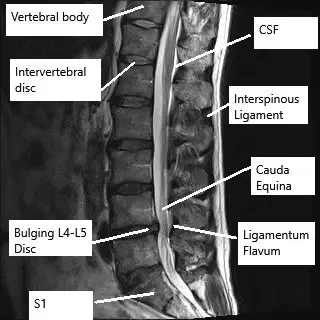

Microdiscectomy is a minimally invasive surgical procedure to help relieve the pressure from pinched nerves known as sciatica or lumbar radiculopathy. Sciatica is most commonly caused by a prolapsed intervertebral disc. During surgery, the spine surgeon removes the protruding intervertebral disc material. The recovery after microdiscectomy surgery is usually faster as compared to open discectomies and lumbar fusion surgeries.

A part of the vertebra known as the lamina may be partially cut to expose the intervertebral disc. The surgeon carefully retracts the spinal nerve roots and uses a special instrument to take small bites of the intervertebral disc. The protruding part of the intervertebral disc is removed and the surgeon carefully closes the incision in layers.